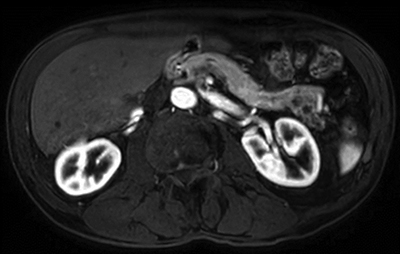

Figure 3

Axial cut in T1 DIXON sequence in arterial phase showing caudal division of the tail of the pancreas and chronic pancreatitis changes.